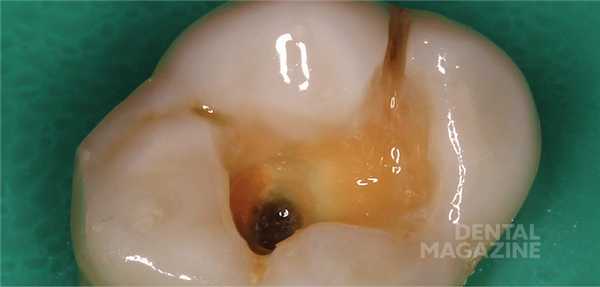

Типичным представителем 1-го класса является кариес фиссур, встречающийся довольно часто. Эта патология очень непредсказуема, и нередко объемы поражения оказывается гораздо больше предполагаемой глубины. Фиссурная форма кариеса, как правило, характеризуется практически полным сохранением жевательной морфологии, и, каким бы высоким ни было мастерство реставратора, мы все равно не сумеем воссоздать жевательную поверхность лучше, чем она была. Поэтому вполне резонно было бы скопировать сохранившуюся анатомию и перенести ее в будущую реставрацию. Реализовать это можно с помощью методики окклюзионного ключа. Основным отличием этого подхода от традиционного варианта восстановления является то, что перед проведением препарирования с жевательной поверхности снимается ключ (небольшой оттиск), которым впоследствии можно было бы отдавить порцию композита для придания ей исходной формы зуба. Наиболее подходящим материалом для изготовления ключа являются твердые bite-силиконы для регистрации прикуса. Они обладают достаточной твердостью, чтобы продавить мельчайшие детали жевательной поверхности, и при этом практически не липнут к композиту.

На рисунке 1 показана исходная ситуация.Классический фиссурный кариес зубов 16 и 17. Как и в большинстве подобных случаев, кариозный процесс протекает абсолютно бессимптомно.